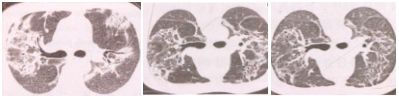

3. 肺泡间质型

双肺磨玻璃影或条索状阴影,可伴有支气管血管束增粗弥漫网格影,伴支气管扩张症。